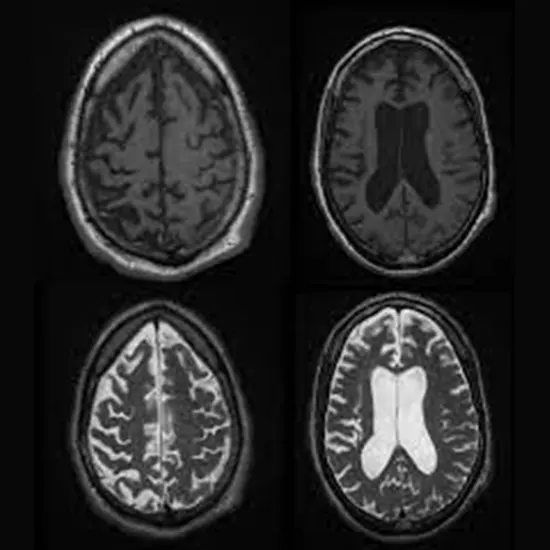

Brain imaging

MRI or CT scans of the talent may additionally be used to appear for attribute modifications in the Genius that are related to the GSS, such as the presence of peculiar protein deposits.